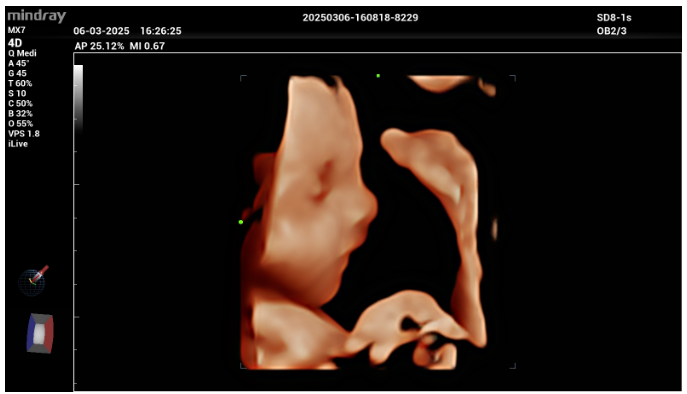

Além disso, a Mindray lançou o recurso que muda a experiência do exame. O iLive dispõe de uma realismo impressionante, superfícies mais definidas, sombreamento natural e visualização emocional do bebê ainda no útero.

O recurso, além da questão emocional, traz detalhamento anatômico com clareza, ajudando no acompanhamento do desenvolvimento fetal e detecção precoce de alterações, resultando em um exame mais completo, humano e focado em quem importa.